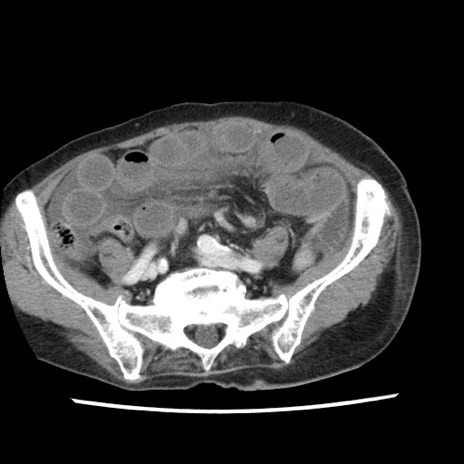

症例1(横断像)

【症例】80歳代女性

【主訴】腹痛

【現病歴】8時間前から腹痛あり来院。

【既往歴】糖尿病、脂質異常症、子宮体癌にて子宮全摘術

【身体所見】意識清明・会話良好だが腹痛で苦悶様、全腹部にわたって反跳痛と圧痛あり

【データ】WBC 13600、CRP 0.14、LDH 224、CK 90